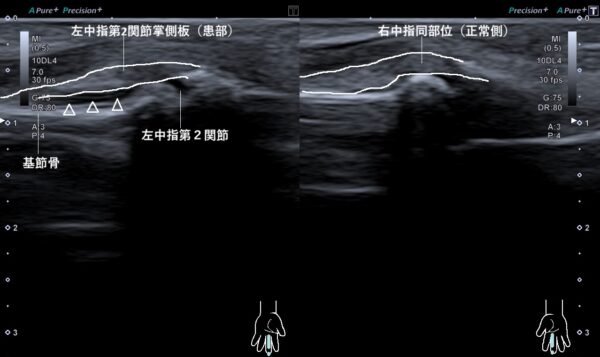

超音波画像観察を行うと第二関節にある掌側板が基節骨から剥離して、そこに血がたまっていました(画像、矢頭の先端の黒い箇所が出血部)。

掌側板は指の関節が過度に反り過ぎないように保護し、関節の動きを安定させる役割がある組織です。

指の突き指(捻挫)をすると、第二関節では掌側板の剥離損傷を起こしやすい場所です。